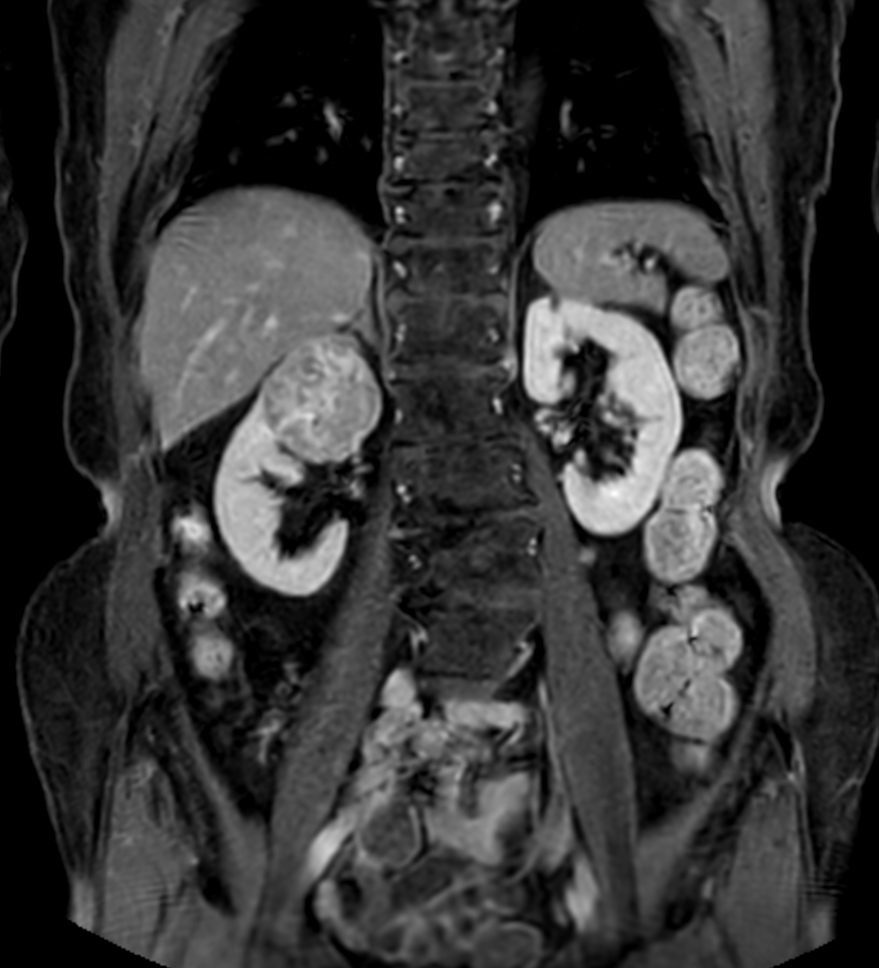

Patient with a kidney lesion. The ExamCard includes techniques for 3D imaging (PelvisVIEW, eTHRIVE) allowing for multiple image directions in one single scan, efficient fat-free imaging over large field-of-views (mDIXON XD), a multi-phase contrast-enhanced sequence (4D FreeBreathing) to improve imaging confidence and Compressed SENSE to accelerate the entire exam.

T1w mDIXON XD FFE (Water only)

T1w mDIXON XD FFE (In Phase)

T1w mDIXON XD FFE (Out Phase)